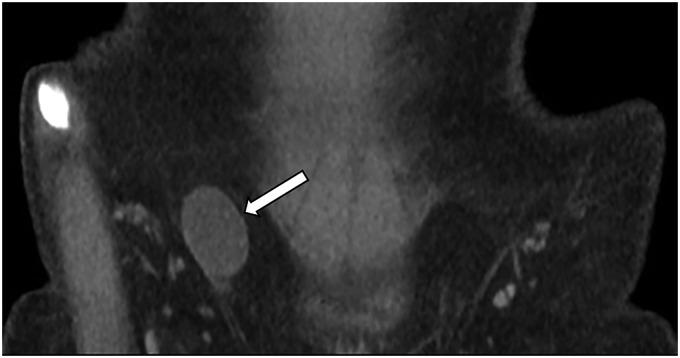

The canal of Nuck, caused by the failed closure of the processus vaginalis in the female, is the continued outpouching of parietal peritoneum through the inguinal canal to the labia majora. Disorders of the canal of Nuck include hernia and hydrocele. Some canal of Nuck hernias, especially of the ovary, may result in emergent complications such as incarceration, strangulation, and ovarian torsion. Knowledge of canal of Nuck disorders and prompt diagnosis are important to avoid serious complications. Imaging, especially ultrasound, is essential for timely diagnosis, leading to appropriate management and better patient care.

女性的努克管是由鞘突未闭引起的,是壁层腹膜经腹股沟管持续向外突出至大阴唇。努克管疾病包括疝和鞘膜积液。一些努克管疝,尤其是卵巢疝,可能导致诸如嵌顿、绞窄和卵巢扭转等紧急并发症。了解努克管疾病并及时诊断对于避免严重并发症很重要。影像学检查,尤其是超声检查,对于及时诊断至关重要,可据此进行适当的治疗并为患者提供更好的护理。